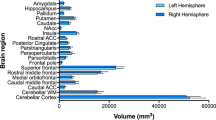

Global FA and MD were not significantly different between groups (P > 0.05). In the ROI-based analysis, and regarding FA, the cingulum was significantly predicted by cardiometabolic variables [R2 adj = 0.31; R2 adj 95% CI = (0.15, 0.46); FDR = 0.015] (Table 3; Fig. 2; Supplementary Fig. S1). Specifically, glycated hemoglobin and BMI z-score were negatively associated with FA (b = − 0.01, P = 0.012; and b = − 0.002, P = 0.0495, respectively). Another WM tract, the IFOF, was significantly associated with glycated hemoglobin (b = − 0.003, P = 0.01), although the model did not overcome FDR correction (FDR = 0.059). Regarding MD, no significant associations were found. Correlations between cardiometabolic and neuroanatomical measures are included in Supplementary Material (Table S4). To second-assess the results obtained in the ROI-based analysis, we did a whole-brain analysis. After applying Bonferroni adjusted threshold for 32 tests (P < 0.0015), no significant associations were found.

a Fractional anisotropy (FA), b mean diffusivity (MD) effect sizes—Cohen’s d—with 95% confidence intervals of lipid and cardiometabolic traits on the cingulum, corona radiata, corpus callosum, inferior fronto-occipital fasciculus (IFOF) and internal capsule. Significant effect sizes are labeled in the X axis with rhombus, circle, triangle, cross and square symbols for cingulum, corona radiata, corpus callosum, IFOF and internal capsule, respectively. After FDR correction, only the FA cingulum model remained significant. Abbreviations: DBP: diastolic blood pressure; HbA1c: glycated hemoglobin; HDL-c: high-density lipoprotein cholesterol; LDL-c: low-density lipoprotein cholesterol; SBP: systolic blood pressure; TG: triglycerides